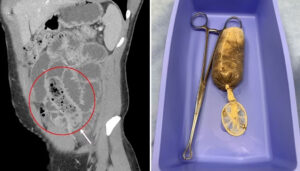

दरअसल, यह घटना अमेरिका के एक शहर की है. डेली मेल की एक रिपोर्ट के मुताबिक इस घटना को एक मेडिकल स्टडी के जरिए बताया गया है. इसमें शख्स की पहचान छिपाई गई है. हालांकि एक्सरे की तस्वीरें और सर्जरी के बाद निकालने के बाद की तस्वीरें जरूर सामने आई हैं. डेली मेल ने अपनी रिपोर्ट में भी इन तस्वीरों का जिक्र करते हुए बताया है कि कैसे डॉक्टरों ने इस मामले को हैंडल किया है.

उसे तत्काल अस्पताल पहुंचाया गया. डॉक्टरों ने जब एक्सरे किया तो उसकी आंत के पास कंडोम में लिपटा केला दिखा. यह आंत का रास्ता रोक रहा था और उसे काफी नुकसान पहुंचा चुका था. करीब एक घंटे तक चले ऑपरेशन के बाद उसे निकाल दिया गया. तीन दिन बाद उस शख्स को अस्पताल से छुट्टी दे दी गई. इसकी तस्वीरें सोशल मीडिया पर वायरल हुई हैं.